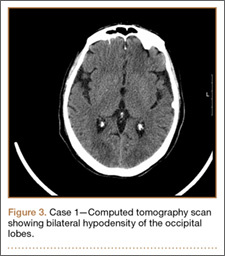

Operative Procedure. After discussions about the risks and benefits of the procedure, the patient underwent posterior spinal fusion from T3 to pelvis (Mesa, K2M) and interbody fusion from L4 to S1 via a presacral approach using the AxiaLIF system (TranS1) (Figure 6). The operation spanned 507 minutes. The patient lost approximately 2200 mL of blood. She was transfused with 1690 mL of blood, 1250 mL of Lactated Ringer’s solution, and 1 unit (50 mL) of albumin. No intraoperative complications occurred.